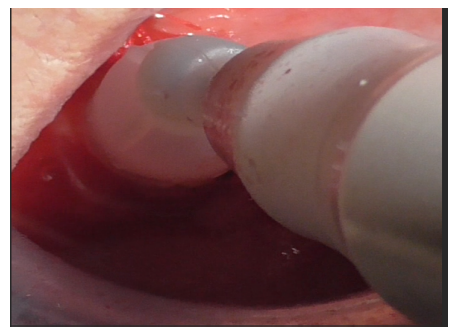

Initially, this insert was used with physiological saline flow (Figure 24) for approximately 1 minute. Subsequently, Ambramicin was applied to the site (Figure 25), capsules were specially opened to use the powdered antibiotic inside, activated for 1 minute using the same bell-shaped insert with physiological saline flow (Figure 26).

Figure 25

Figure 26

After thorough rinsing, EDTA gel was applied to the site (Figure 27) and activated for 1 minute using the bell-shaped insert (Figure 28).

Figure 27

Figure 28